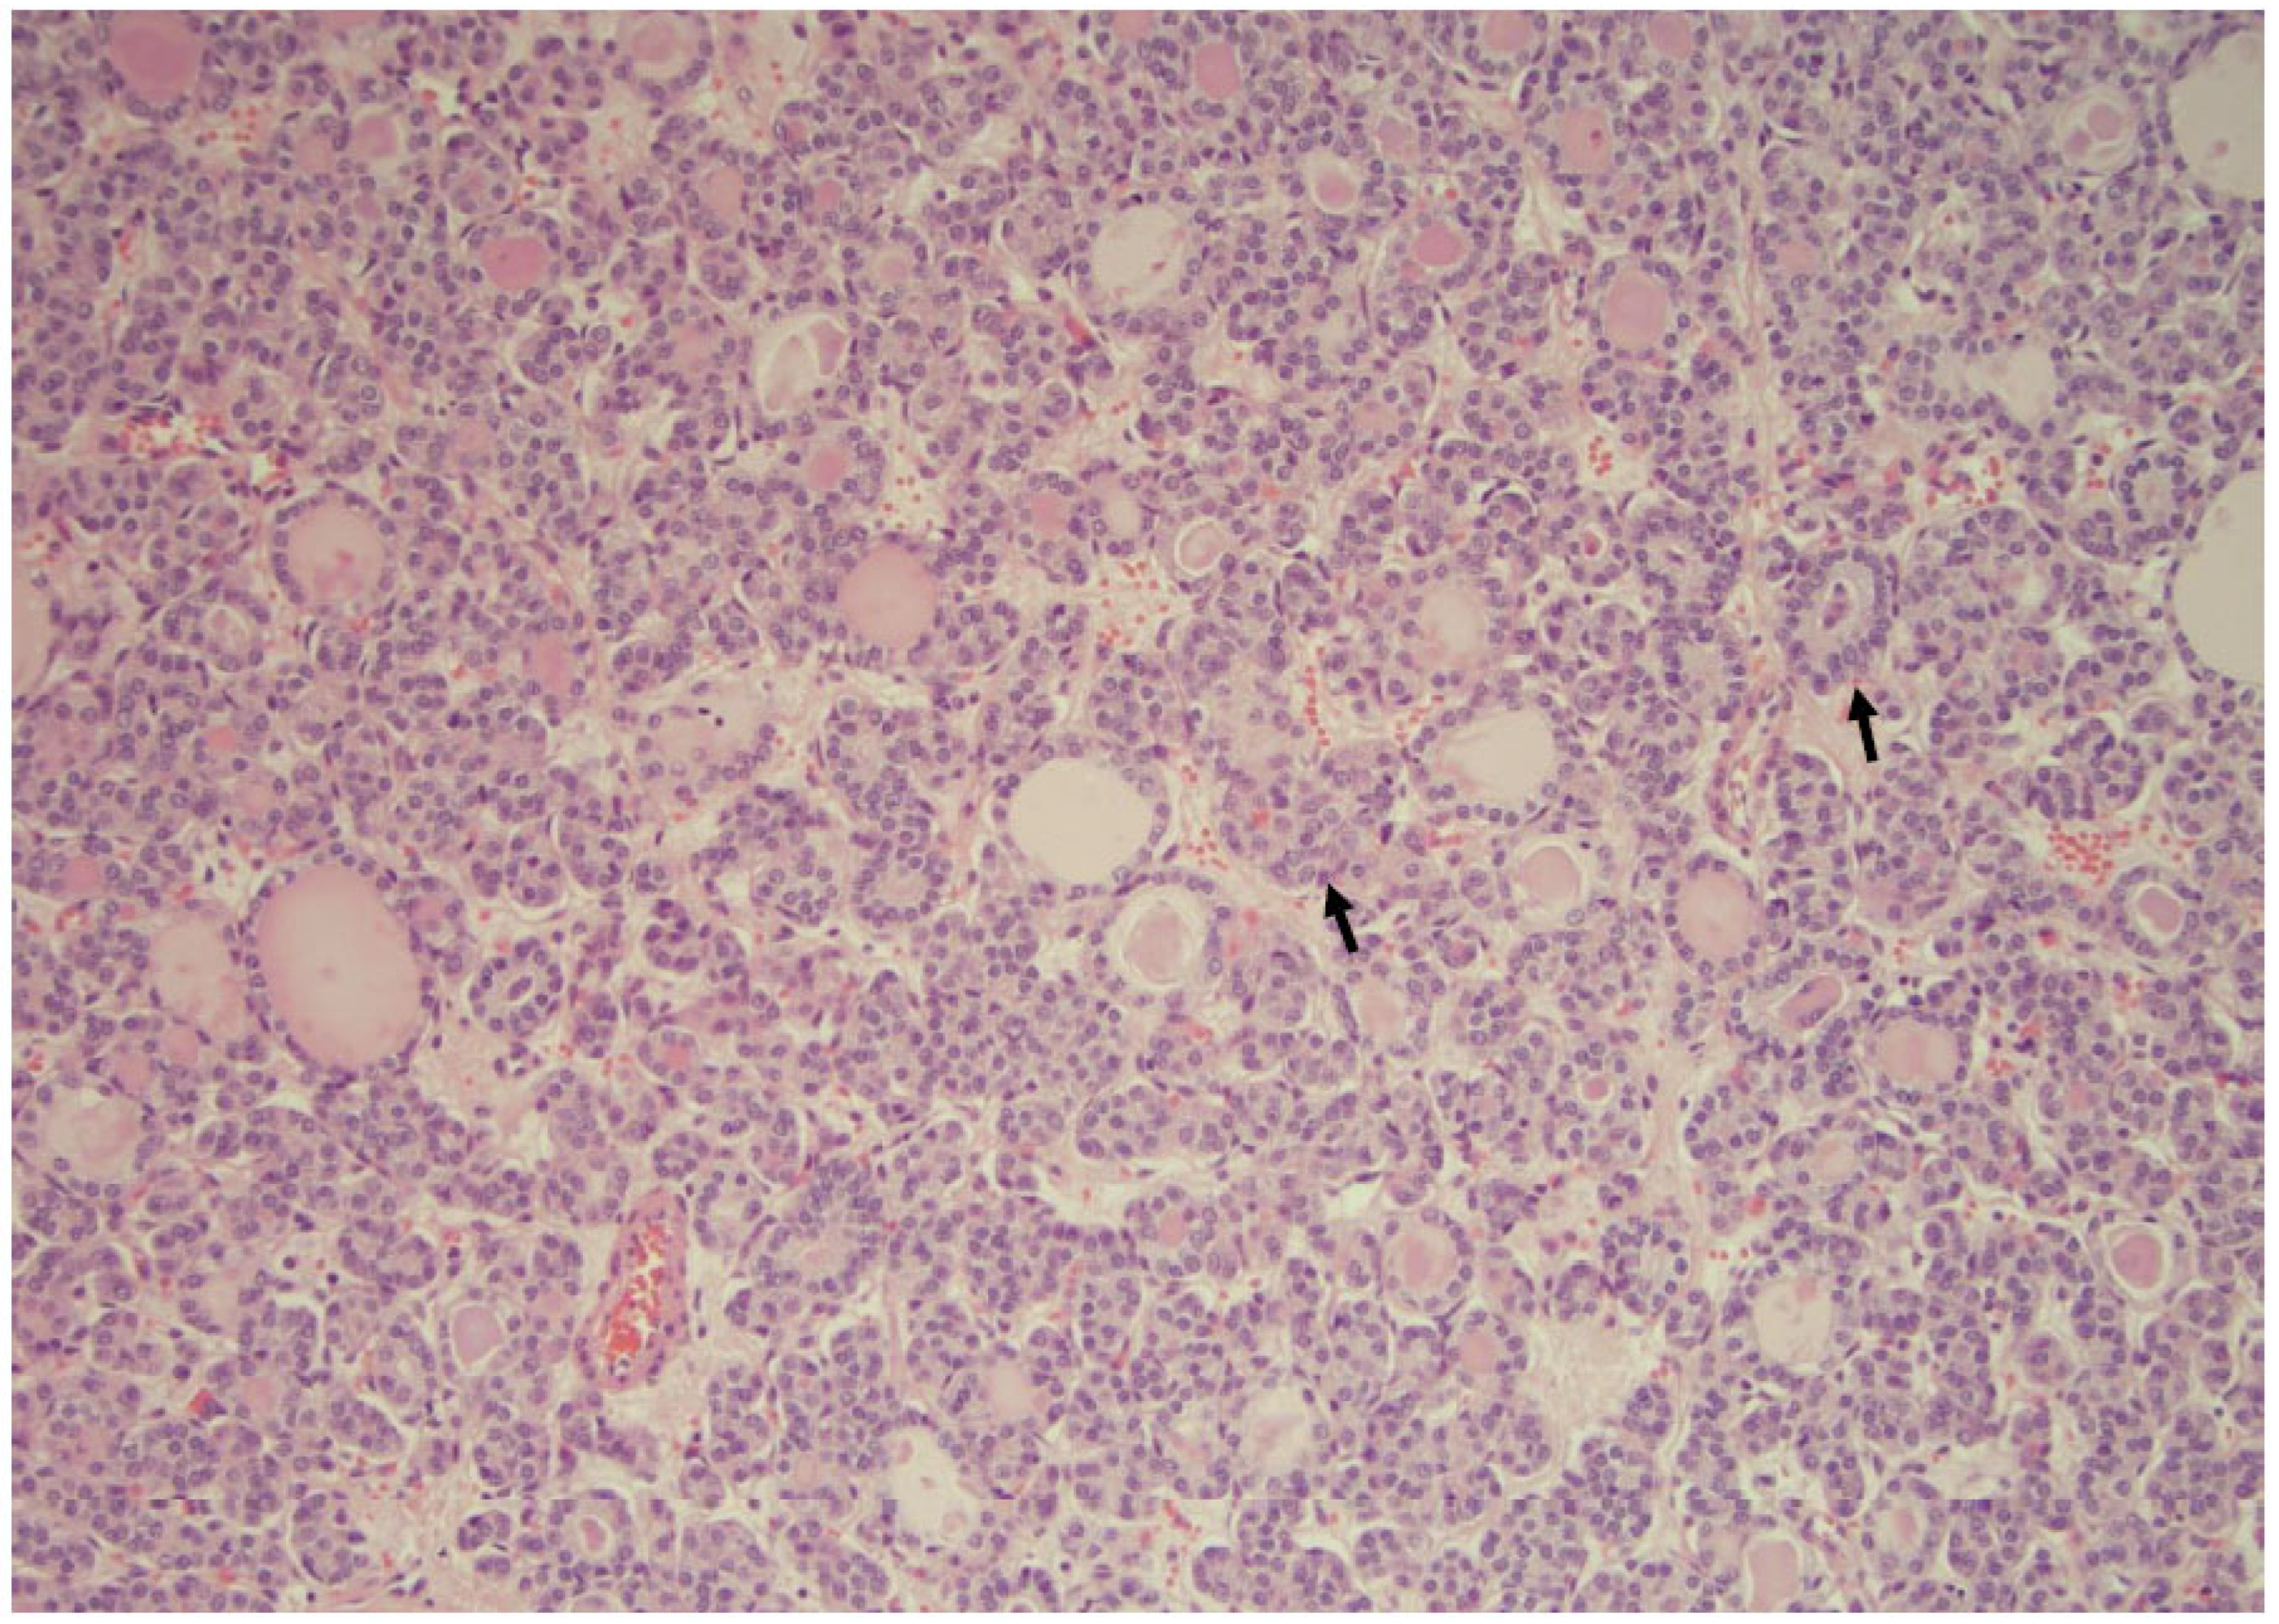

Figure 15. A follicular neoplasm is characterized by numerous microfollicular arrangements (arrows), as seen in this slide, with high cellularity (×200, Papanicolaou stain).